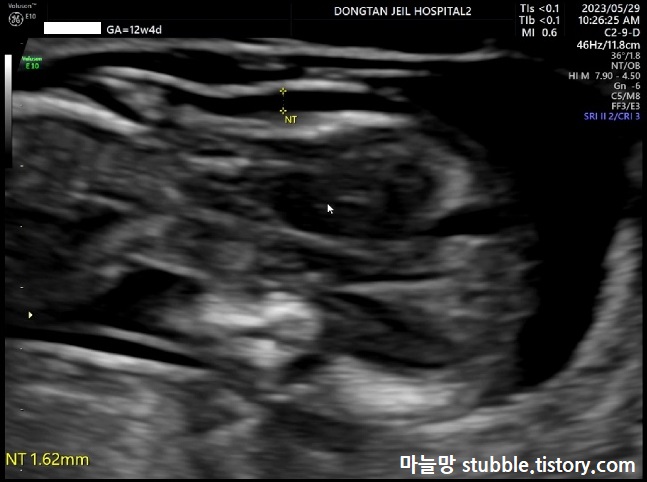

태아 목투명대 (NT) 검사입니다. 보통 아기 CRL(머리에서 엉덩이까지 길이) 4.5cm 이상일때 11주부터 13주 사이에 검사를 하고, 목투명대 길이가 3mm가 넘으면 다운증후군등의 염색체 이상일 확률이 있을 수 있다고 하여 하는 검사 입니다.

계속 엎드려서 아래쪽을 보고 있는 우리 아기입니다.

두근두근!! 우리 아기의 목투명대 길이는 1.62mm가 나왔으므로 안정권입니다.